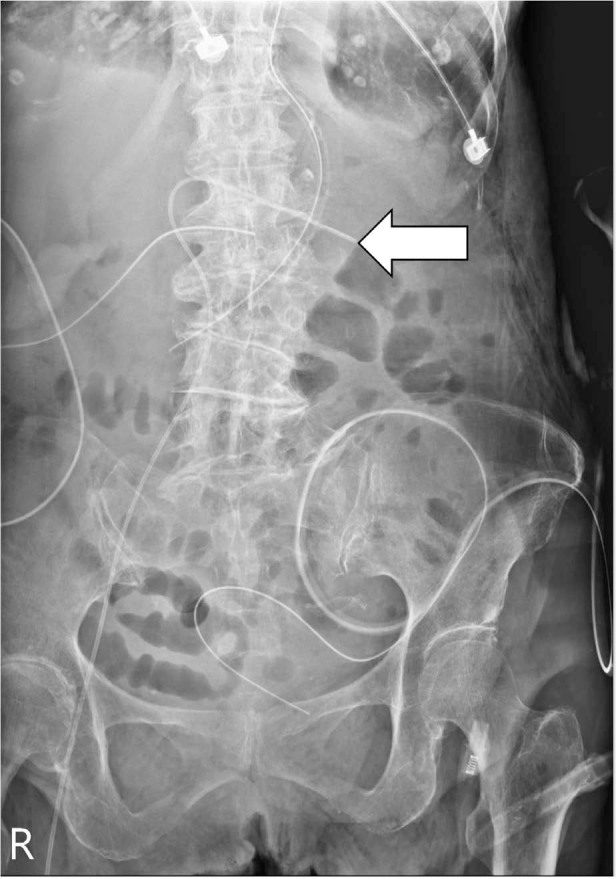

Introduction: Malposition is a relatively rare complication associated with peripherally inserted central catheters (PICCs), particularly in cases of superficial femoral vein (SFV) catheterization. To the best of our knowledge, we are the first to report this rare case of SFV PICC malposition in the contralateral renal vein.

Case presentation: An 82-year-old woman underwent bedside cannulation of the SFV for PICC under ultrasound guidance. Subsequent radiographic examination revealed an unexpected misplacement, with the catheter tip positioned toward the contralateral renal vein. After pulling out the catheter on the basis of the X-ray result, it was observed that the catheter retained its function.

Conclusion: Although rare, tip misplacement should be considered in SFV PICC placement. Prompt correction of the tip position is crucial to prevent catheter malfunction and further catastrophic consequences. For critical patients receiving bedside SFV PICC insertion, postoperational X-ray is crucial for enhancing safety.